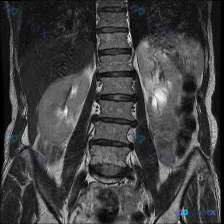

整理到一份腹部MRI冠状位T2加权图像的资料,附带提了一句“脊柱侧弯”,但实际看下来核心发现完全在肾脏上。 先把影像里的关键信息列一下: - 肝脏、脾脏、右肾看起来还好; - 左肾基本被一个大范围的病变占了,正常皮髓质结构不清,边缘也不太规则; - T2信号很杂,有明显的极高信号区(可能是液体、坏死...

刚看到一份有意思的影像资料:提问是“脾脏病变”,但提供的分析却完全是肾脏MRI T2加权冠状位的内容。整理了一下思路和发现,和大家讨论。 --- 先理清楚最核心的矛盾 首先必须明确:基于现有给出的影像信息,完全无法评估脾脏。 报告里只描述了双肾、肾盂肾盏、肾周间隙,压根没提脾脏的大小、信号或结构——...